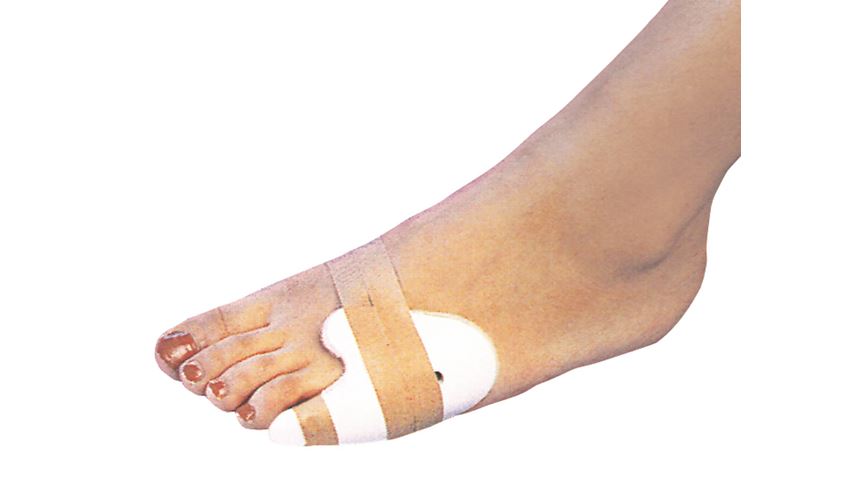

새끼발가락 골절: 스플린트·버디테이핑

왜 스플린트가 유용한가

- 작은 뼈 세 개가 얇게 붙어 있어 정밀 깁스보다 가볍고 효율적

- 인접 발가락과 묶어 충격 흡수

스플린트 선택 기준

- 소재: 경량 알루미늄/폼 패딩

- 길이: 발끝에서 발등 중간까지 완전히 덮을 것

- 굽힘 각도: 10° 이하, 완전 신전 자세 유지

버디테이핑 단계

- 깨끗이 세척 후 건조

- 의료용 테이프 2.5cm 폭, 8 자(∞) 형태로 두 발가락 묶기

- 발바닥 아래 거즈 패드 삽입해 압력 분산

- 2‒3일 간격으로 테이프 교체